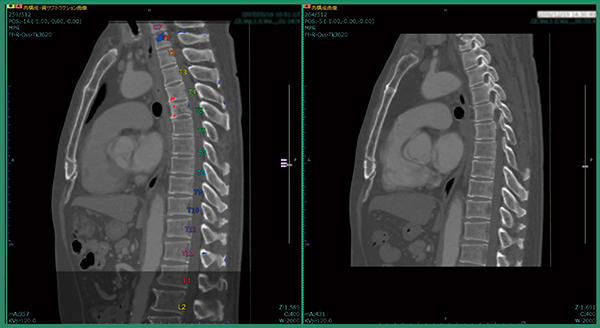

症例1は,肺がん術後症例で肺の形が変形しており,撮影範囲も過去画像は胸部のみ,今回画像は胸腹部と大きく異なっていた。改良版ソフトウエアで差分を取ると,溶骨性の骨転移が青く表示され,椎骨が変形している様子もわかる(図2)。また,自動でラベリングされるため,椎骨番号の判断が容易となり,T4,T5であると判断できる(図3)。さらに,T1にも溶骨性の小さな骨転移があることが明瞭にわかる(図4)。

図3 症例1:椎骨番号の自動ラベリング